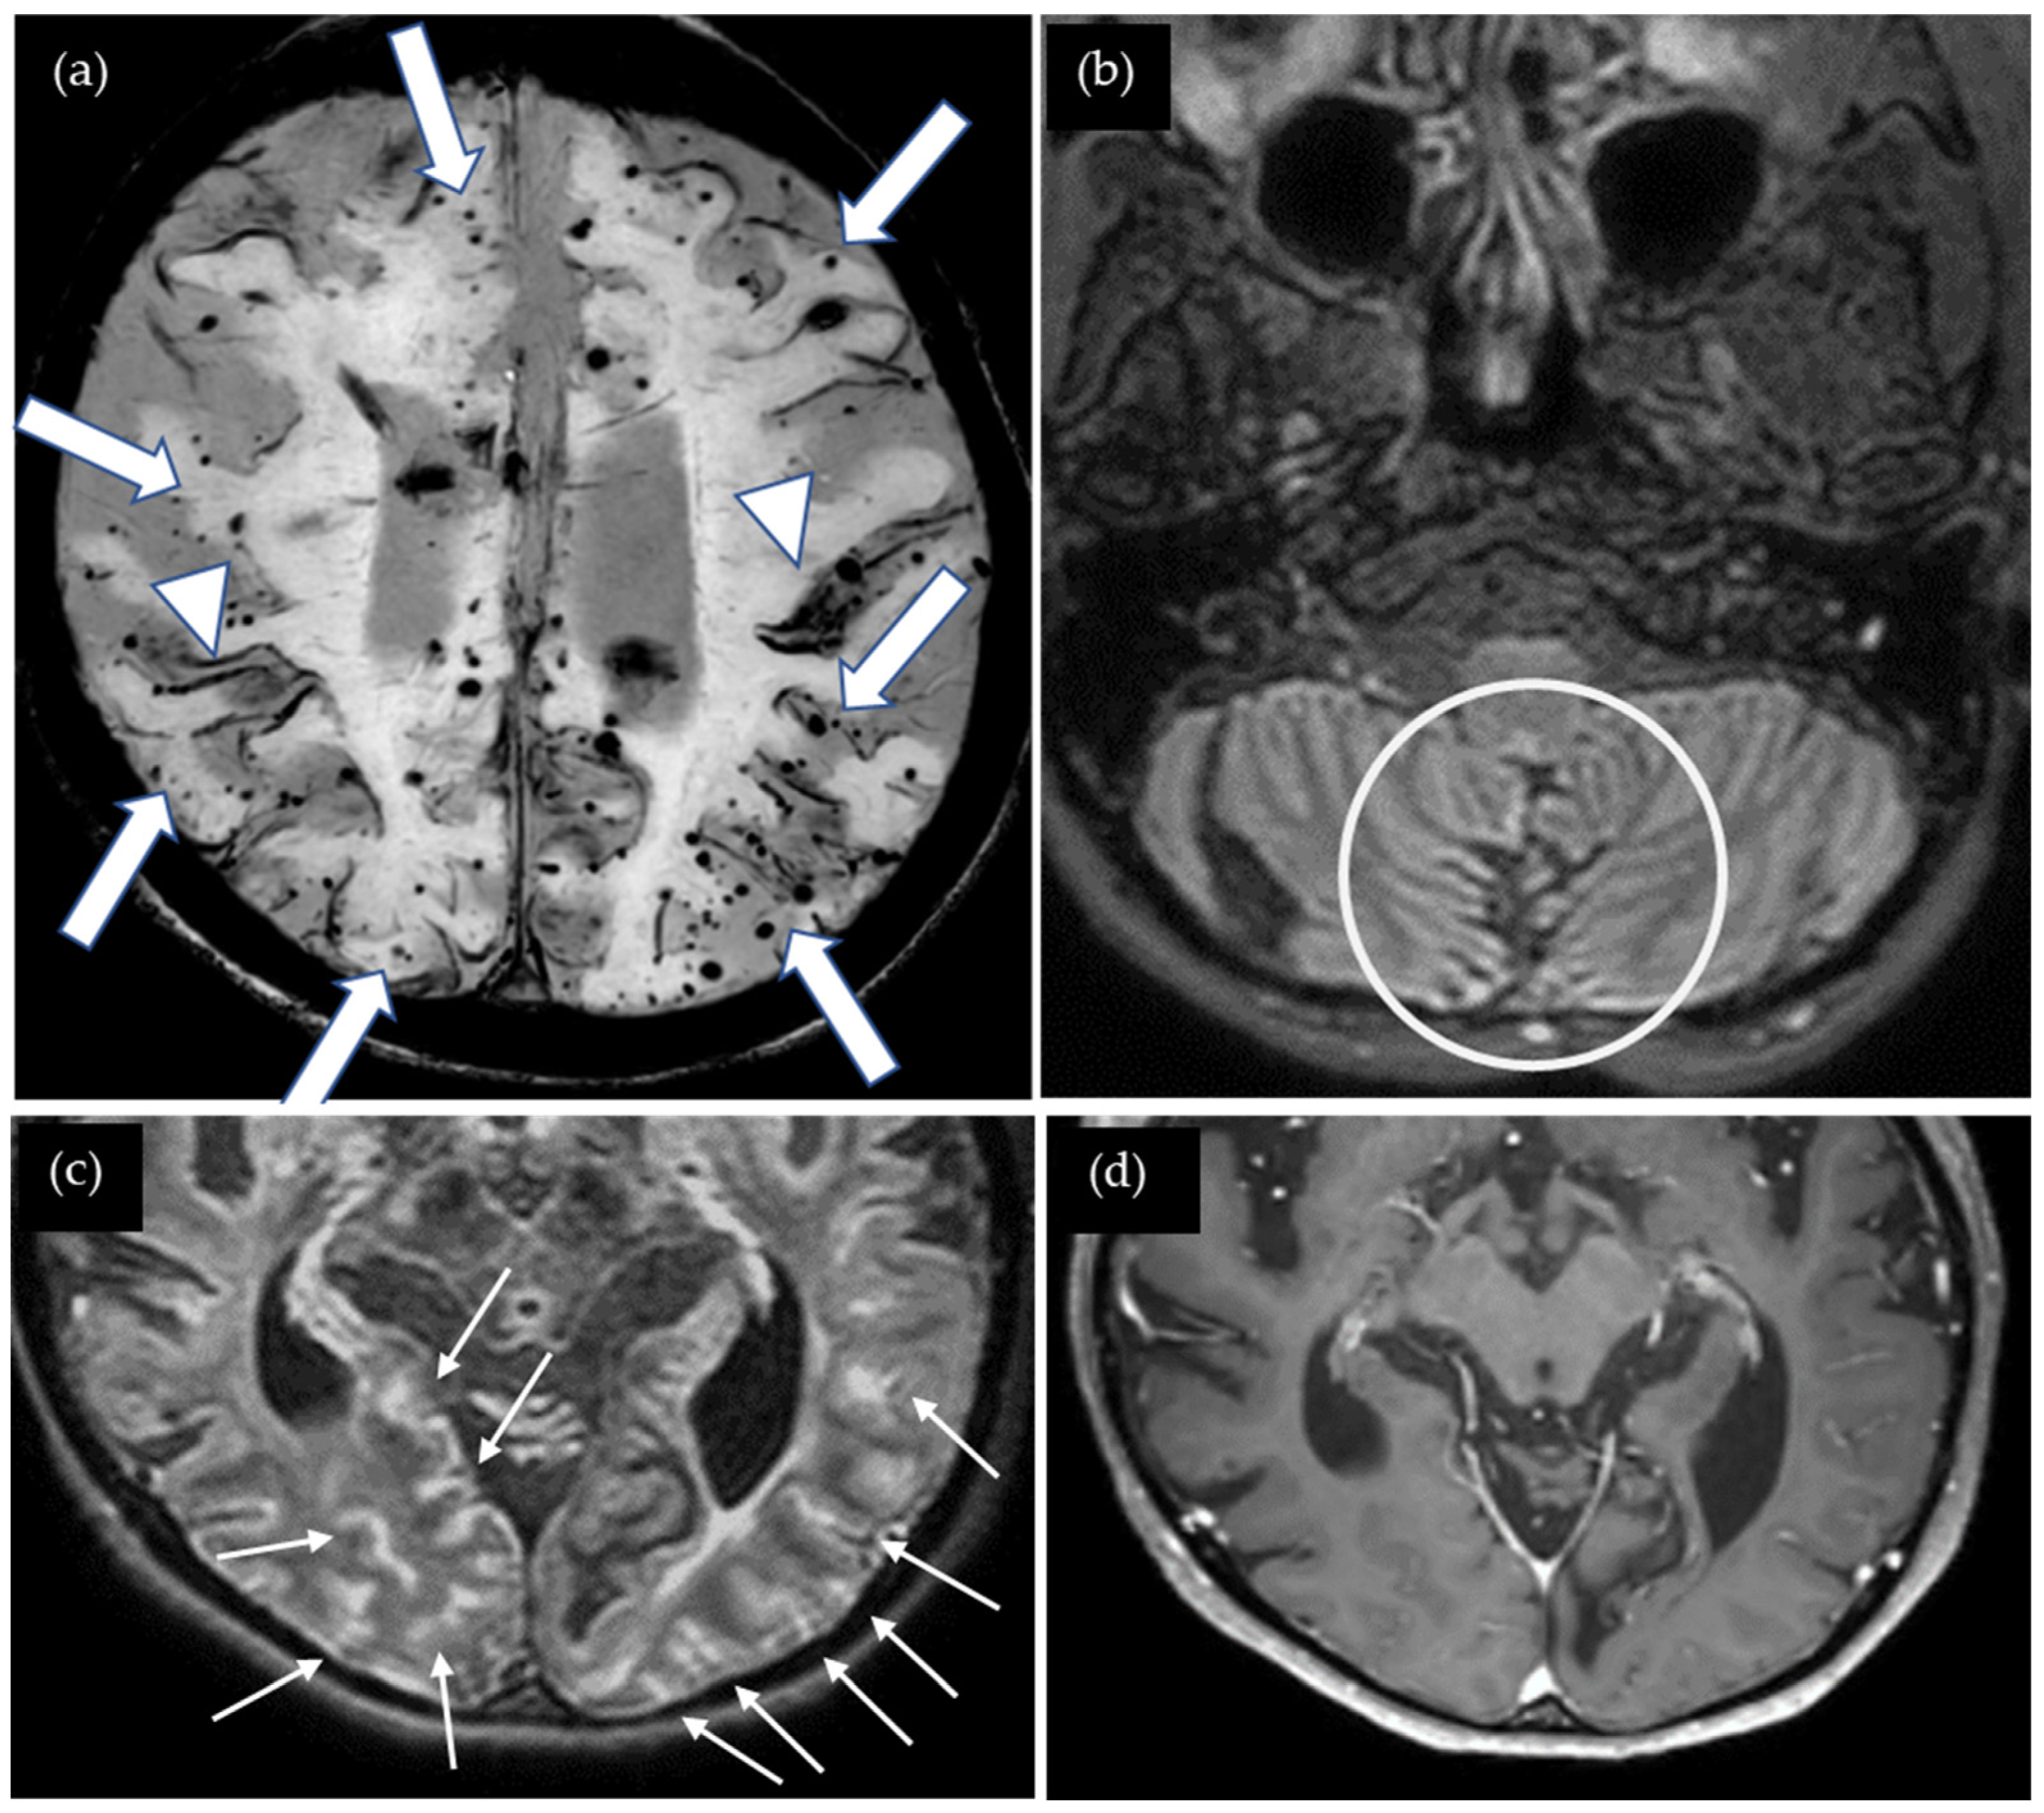

A 47-year-old woman presented with severe cognitive impairment, including episodes of not knowing where her house was, indicative of loss of orientation. Her Mini-Mental State Examination score was 14 out of 30. She underwent surgery for cerebellar medulloblastoma at age five, followed by whole-brain radiation therapy and shunting for obstructive hydrocephalus. Cadaveric dura mater use was not confirmed. She had no history of hypertension or familial CAA. Susceptibility-weighted imaging (SWI) showed multiple cSS in both cerebral hemispheres as well as multiple CMBs located mainly in the cortex, and several microbleeds were detected in the cerebellum (Figure 1). The CAA- SVD score was 5 based on the previous literature [5], consisting of two points for lobar CMBs, two points for cSS, zero points for CSO-PVSs, and one point for WMH. Contrast-enhanced 3D FLAIR showed sulcal enhancement extending from the temporal to occipital lobes bilaterally while enhancement was not detected on the contrast-enhanced 3D gradient echo (GRE) T1-weighted image. Additionally, the T1-weighted image shows global brain atrophy. Neither cerebrospinal fluid (CSF) examination nor amyloid positron emission tomography (PET) was performed. Thus, this case was considered a possible iCAA based on the criteria [1].

Figure 1.

(a) SWI shows numerous lobar cerebral microbleeds (CMBs) (arrows) and cortical superficial siderosis (cSS) (arrow heads); (b) non-contrast 3D FLAIR shows postoperative changes in the cerebellum (circle); (c) contrast-enhanced 3D FLAIR shows sulcal enhancement in the bilateral occipital lobes (small arrows) while enhancement was not detected on (d) the contrast-enhanced 3D gradient echo (GRE) T1-weighted image.